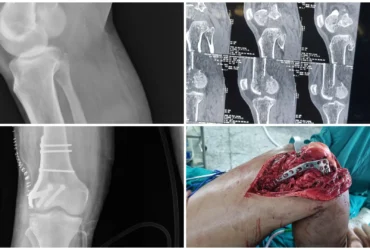

●DEFORMITY CORRECTION

●COMPLICATED FRACTURES

●FAILED FRACTURES

●TRAUMA CARE WITH DEEP ACCURANCY

We Provide Orthopedic Service by Experience Doctors

We has a dedicated multidisciplinary team that cares for and surgically repairs acute fractures for patients of all ages. We offer expertise in fractures of the hip, arm, leg, hand, foot and ankle.

Right PCL Avulsion Fracture Treated with PCL Avulsion Fixation | Balanku Hospital

Huligeppa with right PCL avulsion fracture and knee instability underwent successful PCL avulsion fixation at Balanku Hospital and achieved complete recovery of knee range of...